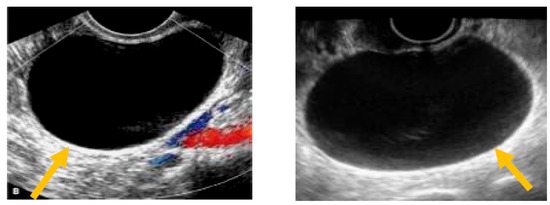

The existence of irregular solid tumors, ascites, at least four papillary structures, an irregular multilocular-solid tumor (diameter at least 10 cm), and very strong blood flow on a color Doppler assessment are malignant indicators, whereas a unilocular cyst, the presence of solid components (max diameter < 7 mm), the presence of an acoustic shadow, a smooth multilocular tumor (max diameter < 10 cm), and the absence of detectable blood flow on the Doppler predispose for the presence of a benign mass [24] (Figure 1, Figure 2 and Figure 3).

Under a Doppler ultrasound, early-stage ovarian cancer displays aberrant central ovarian vascularity, which is distinguishable from the typical hilar or peripheral blood flow [56]. The research found that internal vascularity, low pulsatility indices, and low resistive indices, as measured by a Doppler ultrasound, were linked with ovarian cancer [57,58]. Utilizing a risk score based on sonographic observations, recent research has demonstrated that Doppler-based imaging has an 89% sensitivity and 57% specificity for diagnosing invasive and borderline tumors [57]. The efficacy of transvaginal color Doppler imaging (TVCDI) in detecting ovarian cancer was investigated by a study named “Transvaginal Color Doppler Imaging in the Identification of Ovarian Cancer in a Large Study Population”. In this study, 3845 women with adnexal masses had a preoperative TVCDI evaluation. Using a comparison of preoperative and postoperative histopathological diagnoses, the researchers sought to establish the diagnostic performance of TVCDI in identifying malignant ovarian tumors. For detecting malignant ovarian lesions, TVCDI attained a sensitivity of 91.1%, with a specificity of 88.1%, a positive predictive value of 45.7%, and a negative predictive value of 98.9%. Thus, transvaginal color Doppler imaging is a useful diagnostic tool for the detection of ovarian cancer with a diagnostic accuracy that is superior to grayscale sonography, and its high negative predictive value renders it especially successful at ruling out malignancy when the results are negative [59].

Figure 3. Presence of solid component. (Yellow arrow indicates a multilocular solid cyst with a measurable solid component).